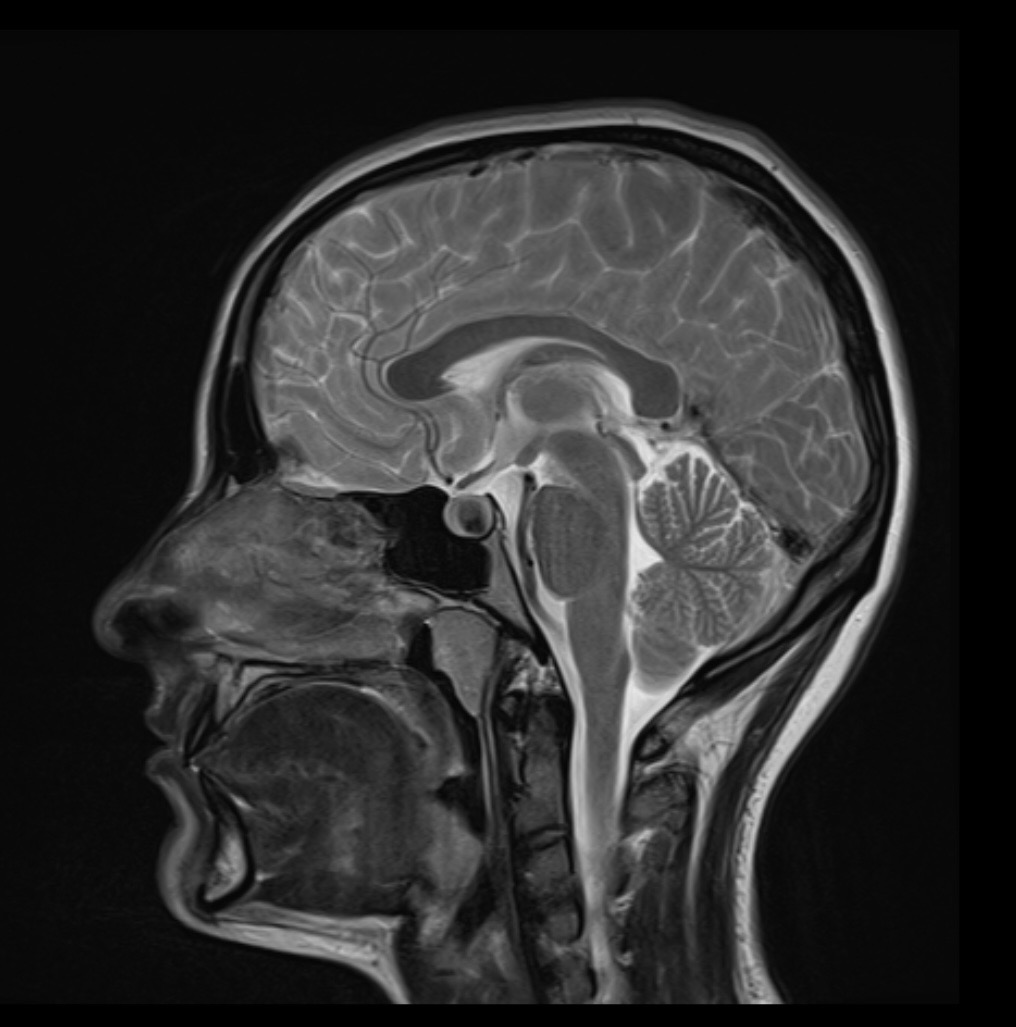

Hola, mi nombre es Geraldine y estoy recaudando fondos para poder realizarme una cirugía para extraer un tumor en la hipófisis, conocido como macroadenoma hipofisiario con apoplejía.

Hace unas semanas comencé con dolores de cabeza intensos, náuseas y vómitos. Tras varios estudios, me diagnosticaron un tumor de 13 mm que ya está afectando mi visión y que requiere una cirugía endoscópica urgente. Sin esta intervención, mi salud podría deteriorarse seriamente.